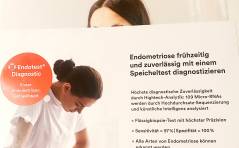

Der „Endotest®“ zur nichtinvasiven Diagnose einer Endometriose: Ready for prime time? PDF DokumentGynäkologische Onkologie up to date